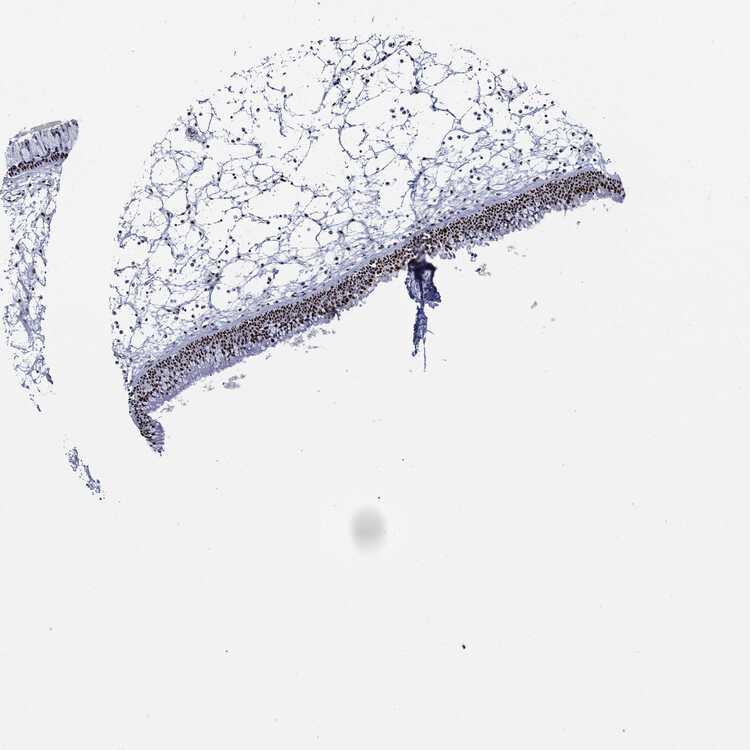

TISSUE PRIMARY DATA NASOPHARYNX Show tissue menu

NASOPHARYNX - Antibody stainingi

Antibody staining in the annotated cell types in the current human tissue is reported as not detected, low, medium, or high, based on conventional immunohistochemistry profiling in selected tissues. This score is based on the combination of the staining intensity and fraction of stained cells.

Each image is clickable and will lead to virtual microscopy that enables deeper exploration of all samples and also displays staining intensity scores, fraction scores and subcellular localization as well as patient and tissue information for each sample.

Antibody HPA030521Antibody HPA030522Antibody HPA030523Antibody CAB080240Antibody CAB080241Antibody CAB080242

Basal cells --Low---

Ciliated cells (cell body) --Not detected---

Ciliated cells (cilia axoneme) --Not detected---

Ciliated cells (ciliary rootlets) --Not detected---

Ciliated cells (tip of cilia) --Not detected---

Goblet cells --Not detected---

Respiratory epithelial cells LowHigh-MediumHighHigh